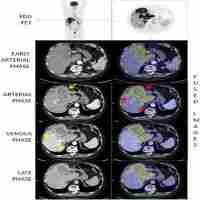

| Abstract | As an antagonist of the JAK/STAT pathway, suppressor of cytokine signaling 3 (SOCS3) plays an integral role in shaping the inflammatory environment, tumorigenesis and disease progression in cholangiocarcinoma (CCA); however, its prognostic significance remains unclear. Although tumor necrosis factor α-induced protein 3 (TNFAIP3, also known as A20) can decrease SOCS3 expression and is involved in the regulation of tumorigenesis in certain malignancies, its role in CCA remains unknown. In this study, we investigated the expression of SOCS3 and A20 in human CCA tissues to assess the prognostic significance of these proteins. The expression of SOCS3 and A20 was initially detected by western blot in 22 cases of freshly frozen CCA tumors with corresponding peritumoral tissues and 22 control normal bile duct tissues. Then, these proteins were investigated in 86 CCA patients by immunohistochemistry (IHC) and were evaluated for their association with clinicopathological parameters in human CCA. The results indicated that SOCS3 expression was significantly lower in CCA tumor tissues than in corresponding peritumoral biliary tissues and normal bile duct tissues. Conversely, A20 was overexpressed in CCA tissues. Thus, an inverse correlation between the expression of SOCS3 and A20 was discovered. Furthermore, patients with low SOCS3 expression or high A20 expression showed a dramatically lower overall survival rate. These proteins were both associated with CCA lymph node metastasis, postoperative recurrence and overall survival rate. However, only A20 showed a significant association with the tumor node metastasis (TNM) stage, while SOCS3 showed a significant association with tumor differentiation. Multivariate Cox analysis revealed that SOCS3 and A20 were independent prognostic indicators for overall survival in CCA. Thus, our study demonstrated that SOCS3 and A20 represent novel prognostic factors for human CCA. |